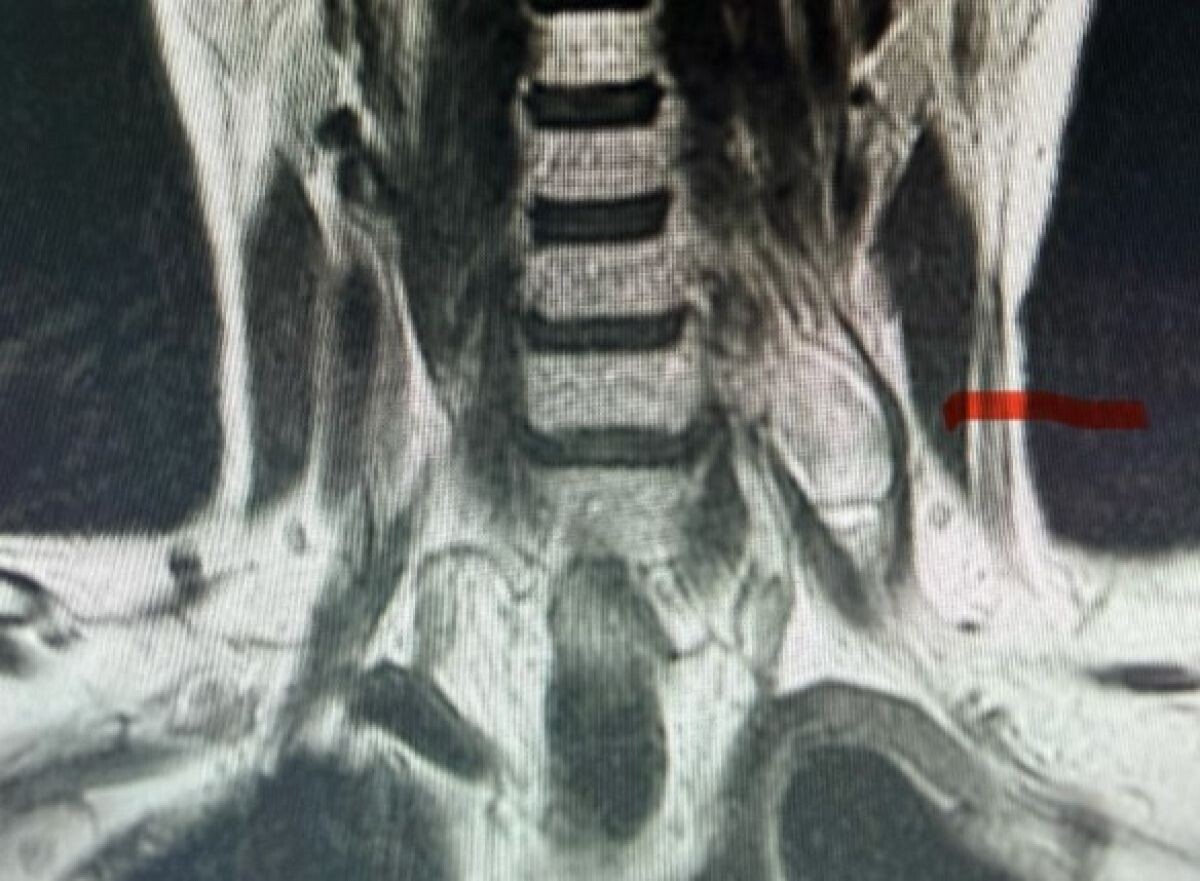

В нейрохирургическом отделении Орловской областной клинической больницы провели сложную операцию по удалению опухоли у 59-летней пациентки. Об этом сообщили на странице медучреждения. Новообразование располагалось в зоне 6-7 шейных позвонков и прилегало к плечевому нервному сплетению, отвечающему за движение руки. У женщины уже развилась выраженная слабость в левой руке. Сложность заключалась в том, что опухоль находилась в миллиметрах от жизненно важных нервных структур. Любое повреждение могло привести к необратимым нарушениям. Операцию под микроскопом выполнил врач-нейрохирург Юрий Серегин. Ему удалось аккуратно отделить опухоль от нервных корешков, не повредив их. После операции у пациентки отступила неврологическая симптоматика, и её выписали из больницы.

Новообразование располагалось в зоне 6-7 шейных позвонков и прилегало к плечевому нервному сплетению, отвечающему за движение руки. У женщины уже развилась выраженная слабость в левой руке.

Сложность заключалась в том, что опухоль находилась в миллиметрах от жизненно важных нервных структур. Любое повреждение могло привести к необратимым нарушениям.